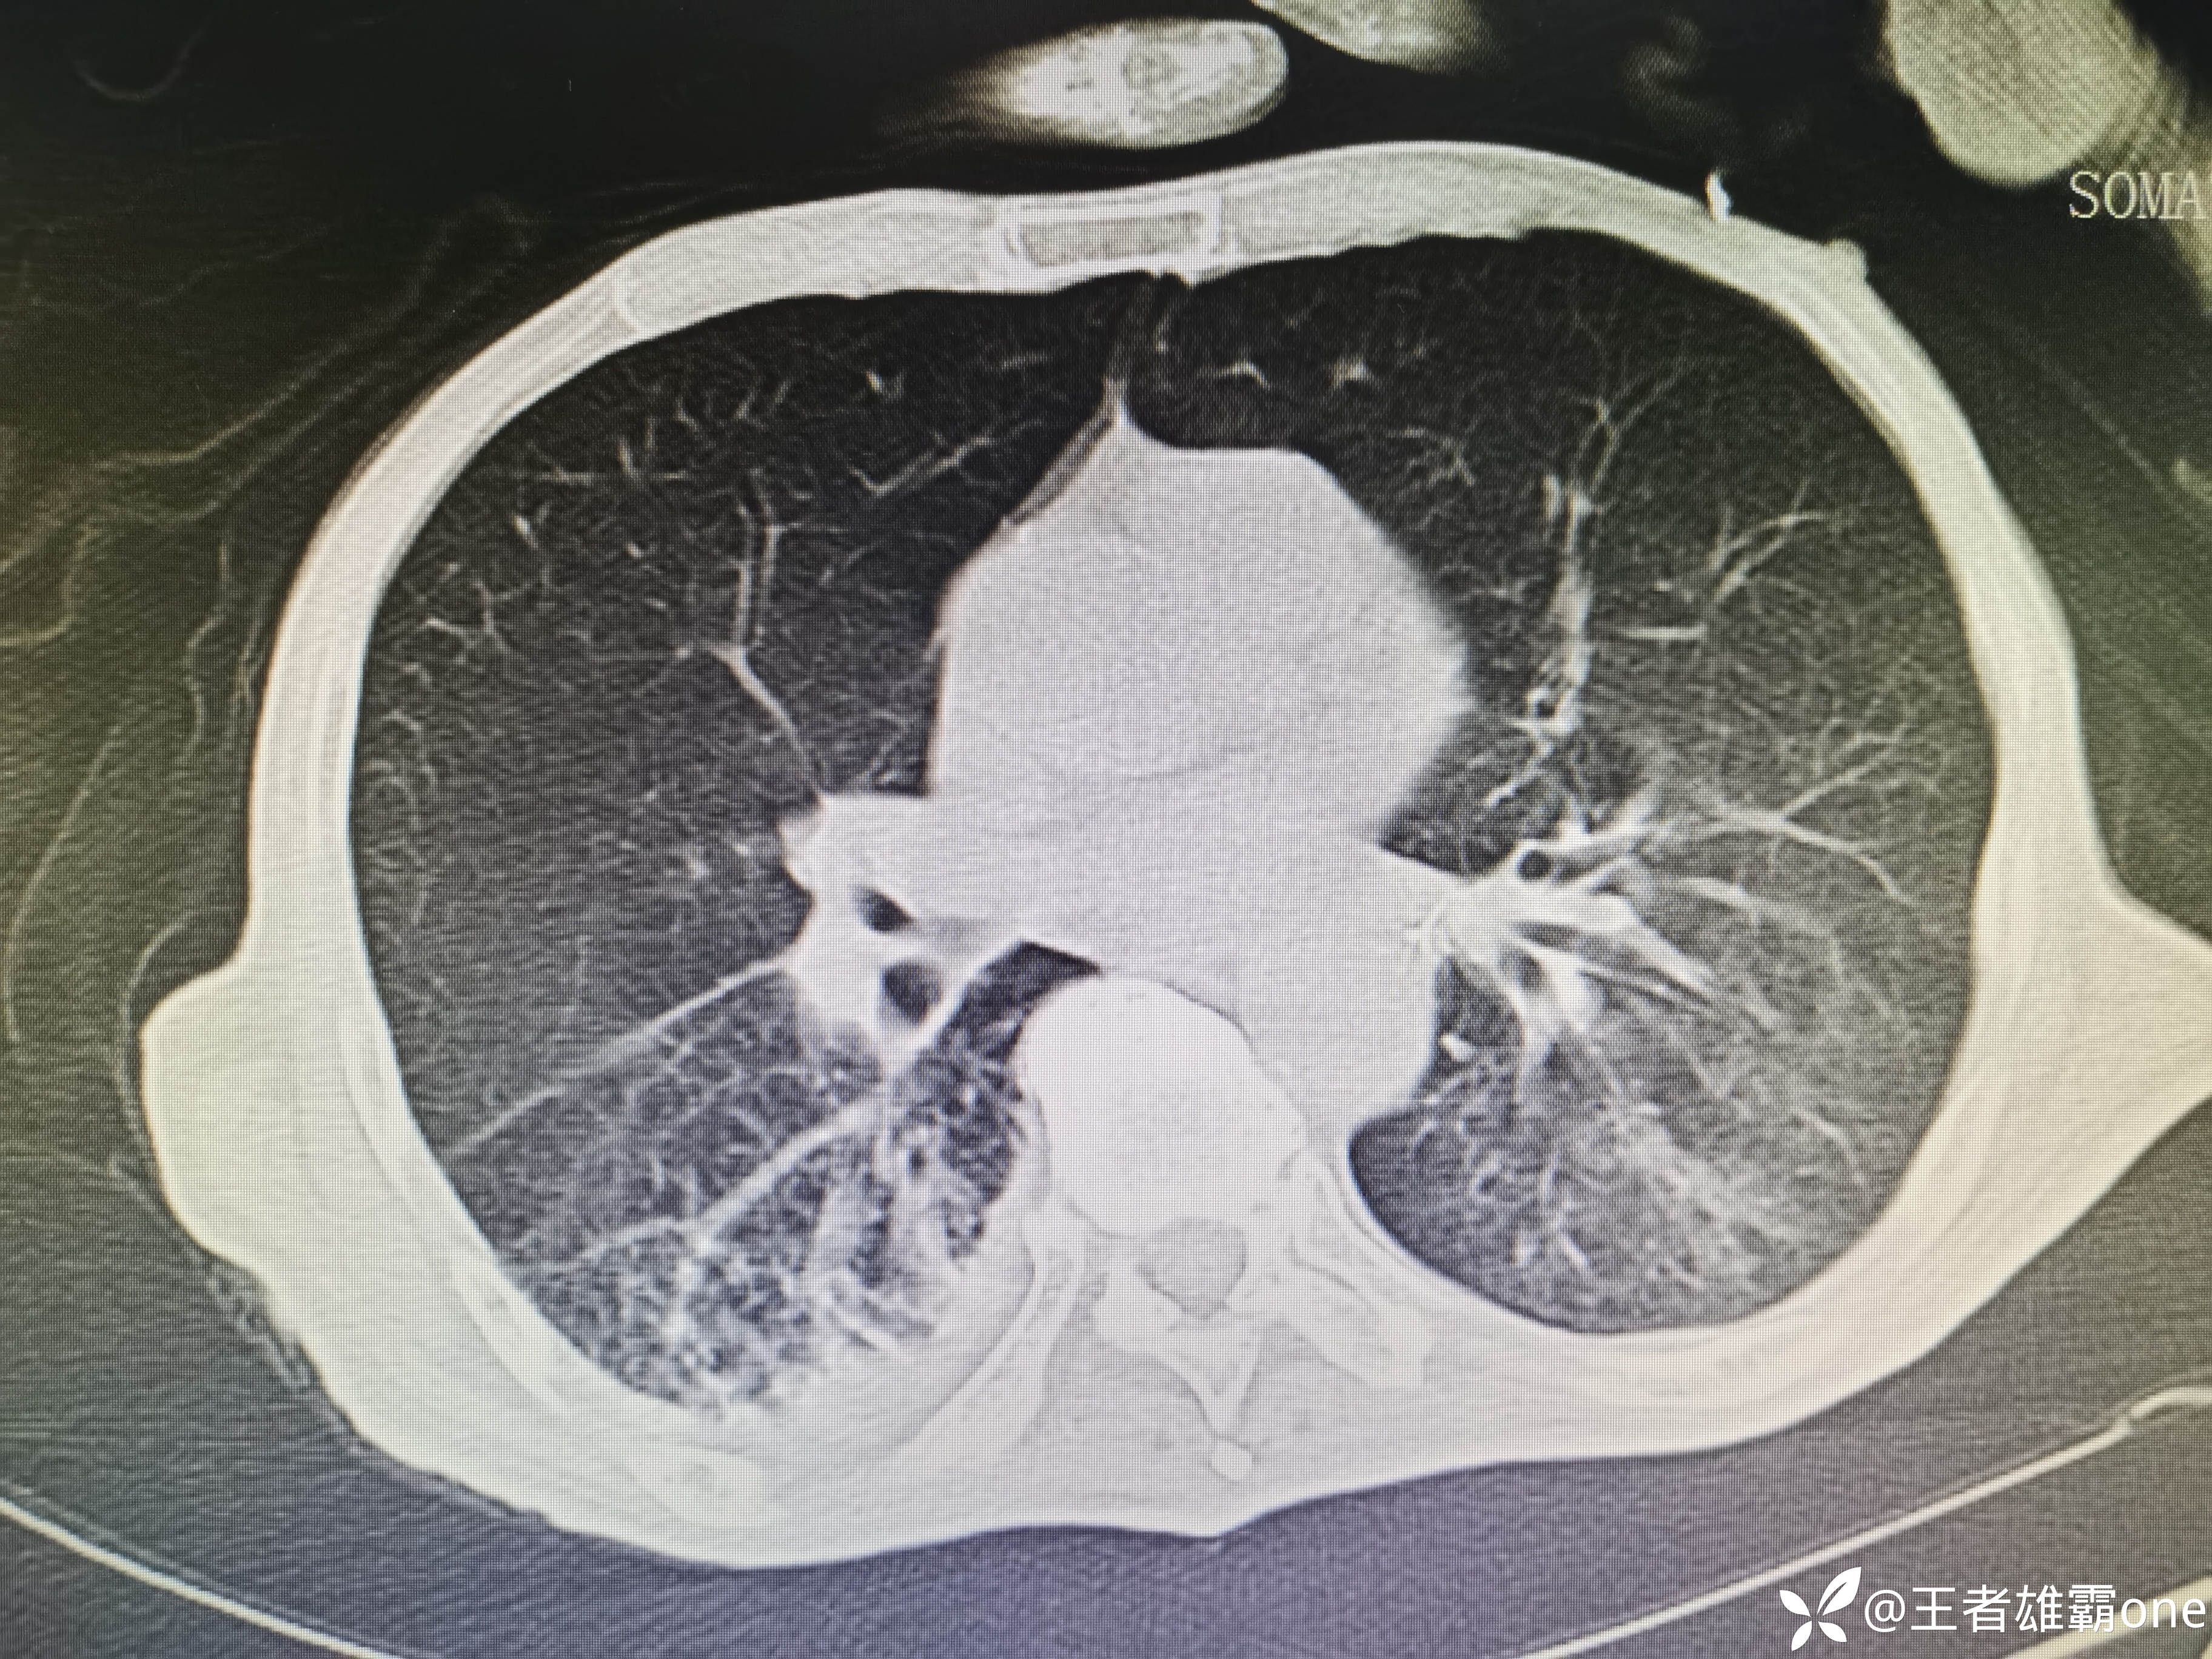

入院时胸部CT:

具体图片: